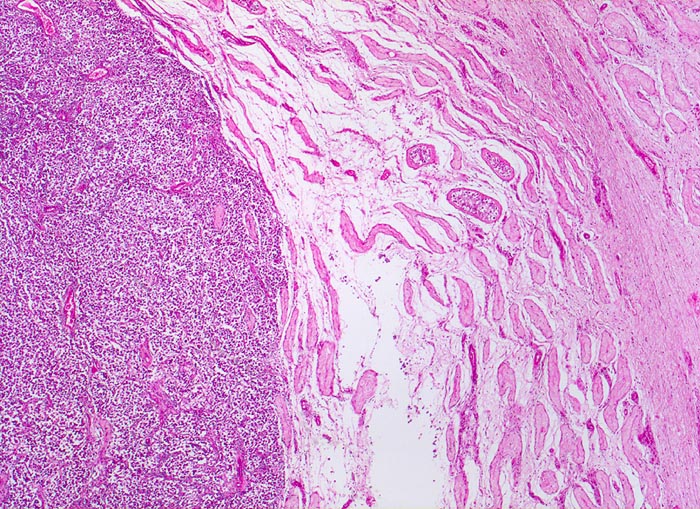

Die Keimzellneoplasie in situ (atypische Keimzellen in Hodentubuli) ist die nicht invasive Vorläuferläsion fast aller Keimzelltumoren beim Erwachsenen (Keimzelltumoren Typ II). Diese kann fast immer in der Nachbarschaft eines invasiven Tumors nachgewiesen werden. Spezifische fortgeschrittenere Formen der Keimzellneoplasie in situ sind das intratubuläre Seminom und das intratubuläre Nicht-Seminom.

• Schmale bindegewebige Septen mit Kapillaren und lymphoplasmazellulärem Entzündungsinfiltrat.

• Tubuläre Atrophie des angrenzenden Hodenparenchyms. Einige Hodentubuli enthalten stark atypische pleomorphe Keimzellen (Keimzellneoplasie in situ).